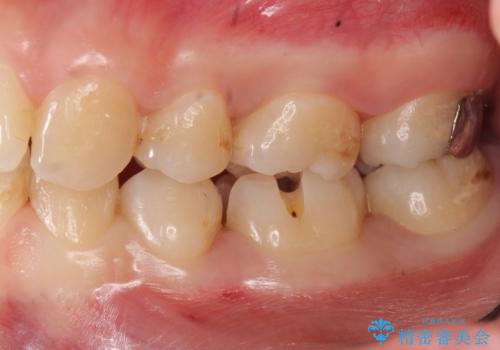

歯と歯の間の虫歯治療 セラミックインレーで治療

- 奥歯の歯と歯の間が虫歯になっていました。

セラミックインレーで治療しました。